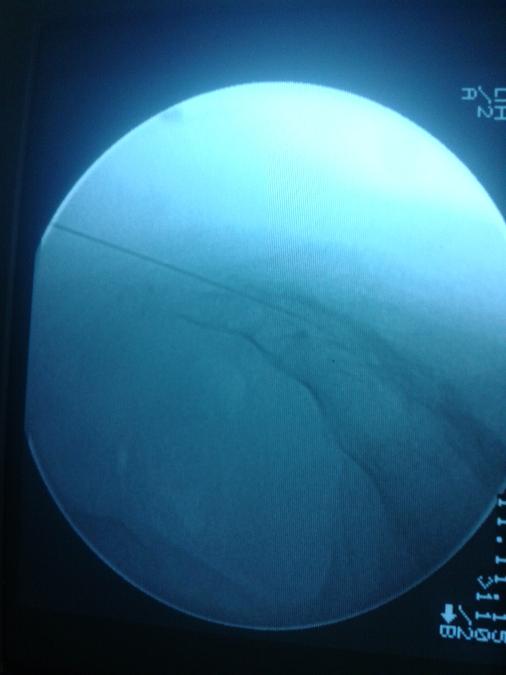

ΜΕΛΕΤΗ ΔΙΑΒΗΤΙΚΟΥ ΠΟΔΙΟΥ:

Διαβητικό πόδιΔιαβητικό έλκος

Ο Ορθοπαιδικός Χειρουργός Δρ. Λαζαρίδης Στέφανος με τη βοήθεια της αλματώδους ανάπτυξης της τεχνολογίας και της εφαρμογής της στην χειρουργική πραγματοποιεί πολύπλοκες και μεγάλες χειρουργικές επεμβάσεις με τον ελάχιστο δυνατό τραυματισμό των ιστών.